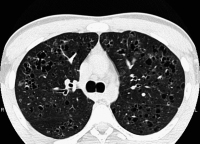

Abbildung 3: Typisches HR-CT-Bild einer späten PLCH

Keywords: CTPLCHPulmonale Langerhanszell-Histiozytose